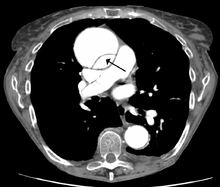

Computed tomography

Computed tomography angiography is a fast, noninvasive test that gives an accurate three-dimensional view of the aorta. These images are produced by taking rapid, thin-cut slices of the chest and abdomen, and combining them in the computer to create cross-sectional slices. To delineate the aorta to the accuracy necessary to make the proper diagnosis, an iodinated contrast material is injected into a peripheral vein. Contrast is injected and the scan performed using a bolus tracking method. This type of scan is timed to an injection to capture the contrast as it enters the aorta. The scan then follows the contrast as it flows though the vessel. It has a sensitivity of 96 to 100% and a specificity of 96 to 100%. Disadvantages include the need for iodinated contrast material and the inability to diagnose the site of the intimal tear.